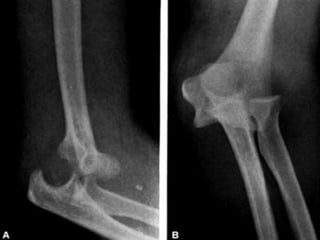

FRATURA SUPRACONDILIANA

DO ÚMERO NA CRIANÇA

FRATURA SUPRACONDILEANA

•COMUM EM CRIANÇAS

•QUEDA COM BRAÇO EXTENDIDO OU EM

FLEXÃO

•PODE TER DESVIO ANTERIOR OU POSTERIOR

EXAME CLÍNICO

•Deformidade (S)

•Edema variável

•Equimose

•Déficit neurovascular

EXAME RADIOGRÁFICO

•Risco de lesão da artéria braquial e do nervo

mediano ou risco de lesão do nervo radial

•Urgência ortopédica

TRATAMENTO

•Fratura sem desvio (TIPO I) – imobilização com aparelho gessado

•Fratura em galho-verde (TIPO II) – redução sob anestesia e

imobilização com aparelho gessado

•Fratura com desvio total (TIPO III) – redução incruenta e fixação

percutânea com fios de Kirschner